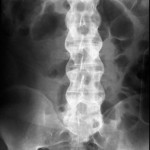

After exam, certain labs can be ordered to check for inflammation (ESR and CRP levels). An HLA-B27 can also be checked through blood work if there is a high suspicion for AS. However, imaging helps greatly in the diagnosis. X-rays can show changes in the SI joint and lumbar spine (such as Bamboo Spine). If it is early in the disease course, an MRI may be needed to catch subtle changes, such as erosions or inflammation.